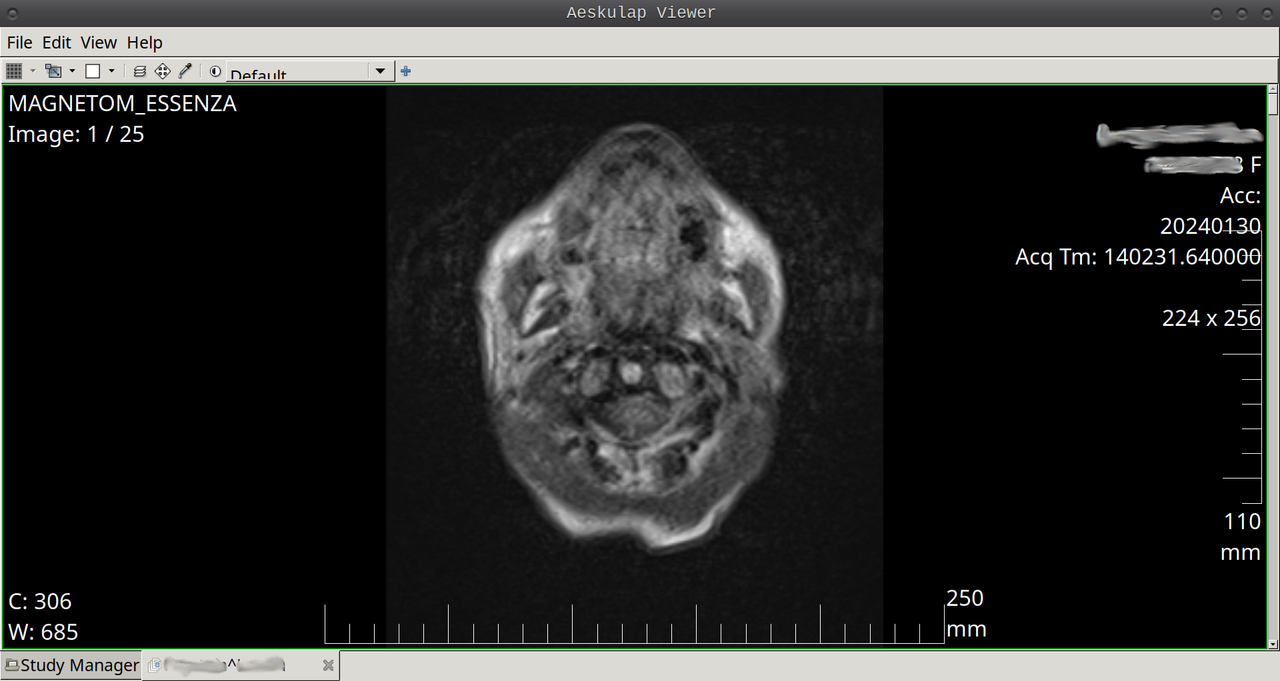

W Debku testowałem 2 programy.

dicomscope poległ na polu chwały nie otwierając niczego.

aeskulap ten działa idealnie, dużo lepiej, niż mDicom.exe na CD.

Automatycznie grupuje zdjęcia na podstawie metadanych, wyświetla w grupach, miodzio.

Wygląda tak:

https://i.postimg.cc/W1G6njvH/Aeskulap-Viewer.png